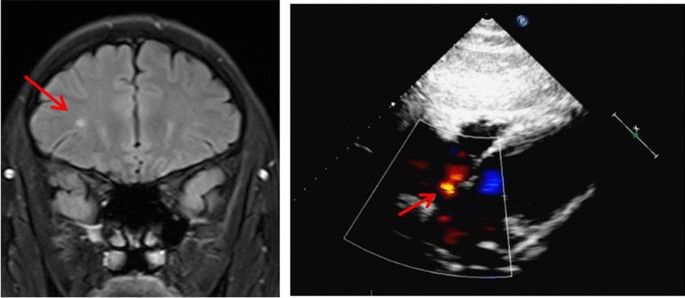

Due to the potential role of PFO in brain ischemia lesions, we analyzed the correlation between PFO and brain ischemia lesions in PFO and control groups and found a highly significant increase in the percentage of cases with brain ischemia lesions in the PFO group compared with the control group (p < 0.001). Of the 100 cases with PFO, 71 cases were present with brain ischemia lesions (case example showed in Fig. 1). The percentage of brain ischemia lesion positive cases in the control group was only 19% (Table 2). This more than threefold increase in the incidence rate of brain ischemia lesions in the PFO group compared to the control group [RR = 3.737 (95%CI 2.496 to 5.767)] was a strong indication of the close correlation between PFO and brain ischemia lesion, suggesting a potential role of PFO in inducing brain ischemia lesion.

Example of a case with PFO and one brain ischemic lesion. One Tibetan male patient with age 32 years, is a resident in an area over 3200 m above sea level with a long-term headache symptom. Left panel, brain MRI shows high-intensity signal by a coronal section on FLAIR. Right panel: echocardiography imaging of the heart. Arrow points to PFO with a diameter of 3.4 mm